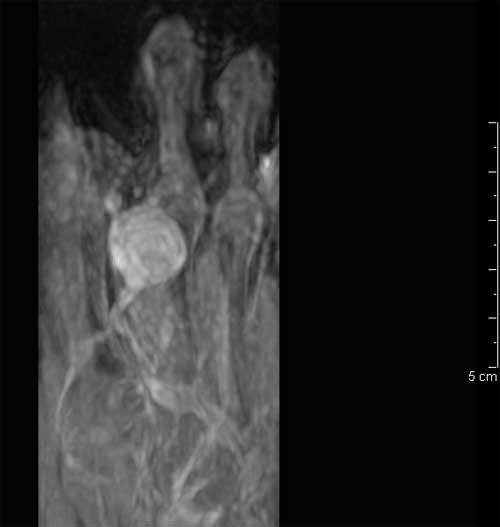

Figura 3. Presenza di flusso in parete. � stata effettuata una RMN con contrasto con acquisizioni multiplanari T1 e T2 pesate anche con tecnica di soppressione del grasso, con il rilievo di una formazione ovalare di 16 x 12 x 20 mm a margini regolari con iperintensit� di segnale centrale nelle pesate T1 e T2 dipendenti, e componente periferica sottile che subisce enhancement contrastografico, in apparente continuit� anatomica con struttura vascolare del fascio vascolo-nervoso dorsale, ascrivibile, in primis, a formazione vascolare o patologia vascolare dilatativa trombizzata (Figure 4, 5 e 6). ![]() |

Figura 4. Angio-RMN Scansione assiale T1 pesata SE. |